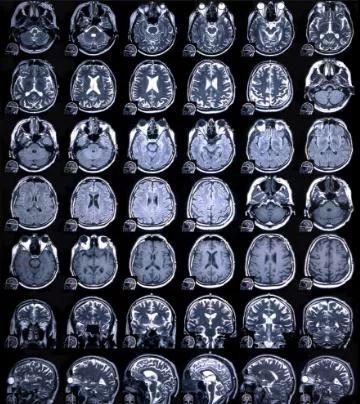

问题四:优选套餐里加做的头部及颈椎的磁共振主要看什么,有什么意义?

答:对于脑的显示,磁共振十分优越,可以看梗塞、肿瘤、出血、畸形等众多脑部疾病,并且脑部疾病大多可无症状,不管年轻人还是老年人,磁共振检查都可以发现脑内绝大多数疾病,尤其是对于一些(如动脉瘤等)无症状但有生命威胁的隐患病症发现并及时治疗。同时,一些看似头部的症状(例如头晕、眩晕等),有时其实是颈椎或脊髓的问题,从而头颈配合检查,可以更加精确诊断、更大程度避免病变遗漏。